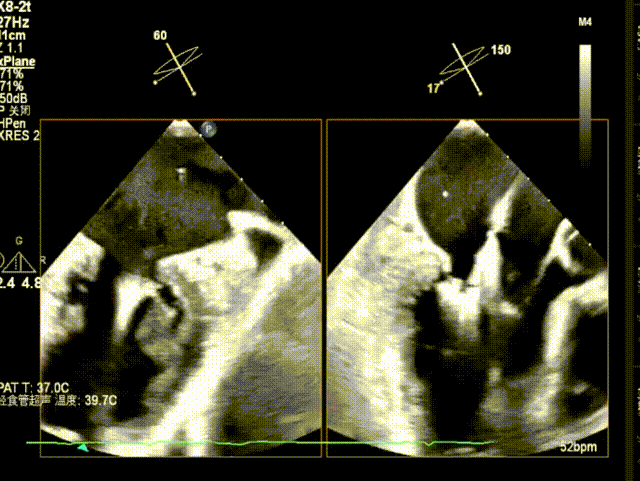

X-plane视窗可见二尖瓣瓣叶“连枷样”运动;

3D enface view示二尖瓣内后叶2偏1区瓣尖可见断裂的腱索呈“连枷样”运动,偏心性返流

PISA定量:EROA=1.06cm²,Rvol=145ml,Vmax=399cm/s

PW显示左肺静脉收缩期血流频谱呈逆向

3D模式测量二尖瓣瓣口面积5.62cm²术前TEE房间隔高度约4.72cm